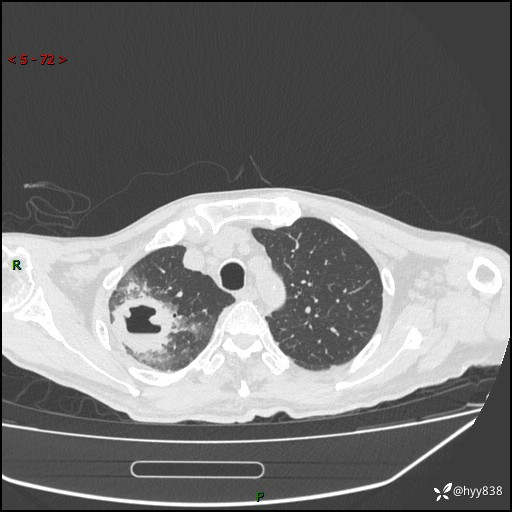

一个月后第二次CT检查(常规抗感染,患者不配合:增强、住院---)